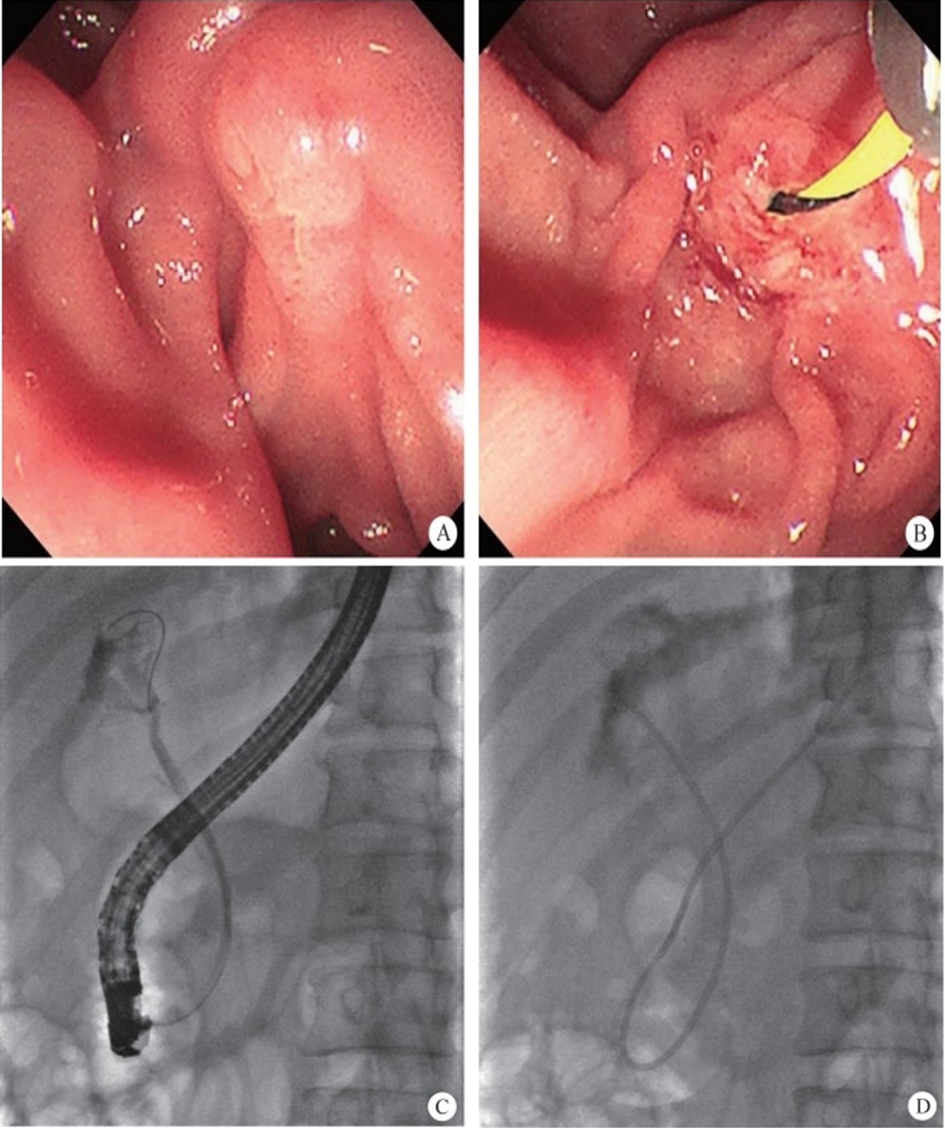

3. Retrograde transpancreatobiliary endoscopy. Super minimally invasive surgery via this channel includes endoscopic surgeries aimed at performing endoscopic lithotomy of the pancreatic biliary system, stent implantation, and biopsy, etc., via the duodenal papilla. The pancreatic duct runs through the entire length of the pancreas; its diameter gradually increases from left to right; the bile duct mainly includes the gallbladder duct, the hepatic duct and the common bile duct, etc. The pancreatic duct joins the bile duct and opens at the descending part of the duodenum, with the sphincter of Oddi surrounding the opening.

The normal common bile duct pressure is 10–15 mmHg (1 mmHg = 0.133 kPa) higher than that of the duodenum, but the basal pressure of the sphincter of Oddi is about 4 mmHg higher than that of the pancreatic biliary system, so that the sphincter of Oddi can effectively prevent the regurgitation of duodenal contents and avoid gastrointestinal bacterial retrograde infection. EST is usually performed before duodenal papillary intubation, which damages the integrity of the sphincter of Oddi, leading to sphincter relaxation and a loss of the anti-reflux physiological function. In 2020, a study was conducted to investigate the feasibility and effectiveness of duodenoplasty to restore the function of the sphincter of Oddi. The study prospectively included 30 patients who had undergone EST lithotomy and duodenal papilloplasty; 80% of patients had a basal pressure of the sphincter of Oddi after duodenal papilloplasty >10 mmHg, and the pressure parameter was resumed after the operation, and was unrelated to the healing process. Postoperative mild pancreatitis occurred in six cases, and a recurrence of the stone in one case. Studies have shown that duodenal papilloplasty can restore the basal pressure of the sphincter of Oddi, thus restoring its anti-reflux function and possibly preventing the reappearence of gallstones and cholangitis.